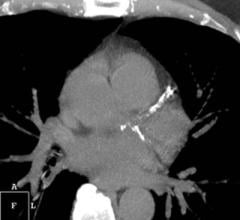

Johns Hopkins researchers say a heart imaging study of scores of pregnant women with the most severe and dangerous form preeclampsia further proves the condition mainly damages the heart’s ability to relax between contractions, making the organ overworked and poor at pumping blood.